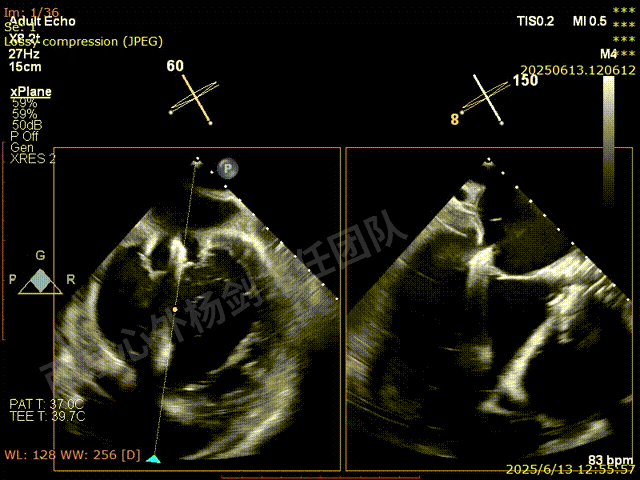

二尖瓣后叶栓系严重,前叶相对错位,反流束沿2区分布广泛,2偏3区处存在反流。

反流宽度至少23mm,因影像调整困难,考虑实际反流更宽。